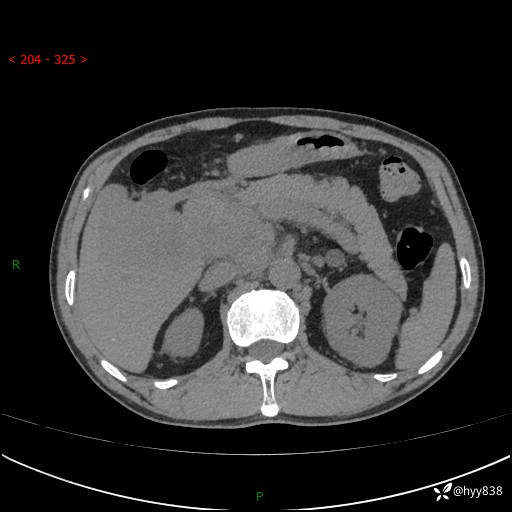

上腹部CT平扫+增强(两期)